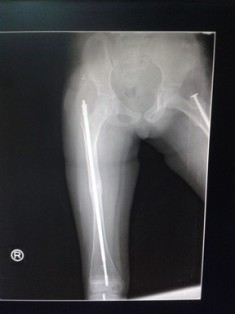

Surgical management: Children will have deformity of long bones because of bending and repeated fractures. Surgical correction of deformity and intramedullary rodding techniques can be used to correct the deformities and prevent refractures. Newer elongating rods are available which decreases the need for repeated surgery. After 18 years the risk of fractures decreases.